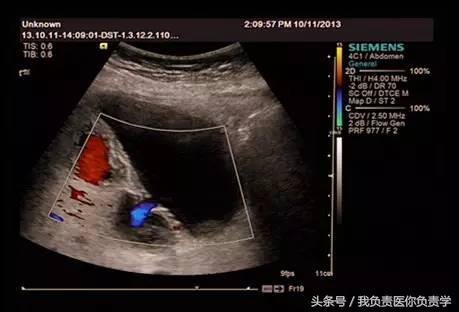

患者女,68岁,因上腹部痛 8天就诊 。超声检查发现胆囊体积明显增大,内部透声差,囊壁明显增厚,胆囊周围可见不规则分布的液性暗区。胆囊壁局部回声中断,探头加压及松开时,CDFI可见中断处出现因液体进出胆囊而导致的多普勒信号。患者行胆囊切除术,术后证实为胆囊穿孔。

图3-图6示胆囊壁局部回声中断,探头加压及松开时CDFI可见红色及蓝色多普勒信号